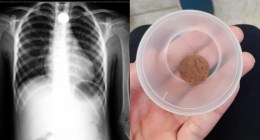

Menino de 8 anos fica com moeda presa na garganta e pai conta que caso é ‘milagre’

A moeda ficou entalada na garganta do menino por 18 horas e só foi retirada por meio de um procedimento médico.